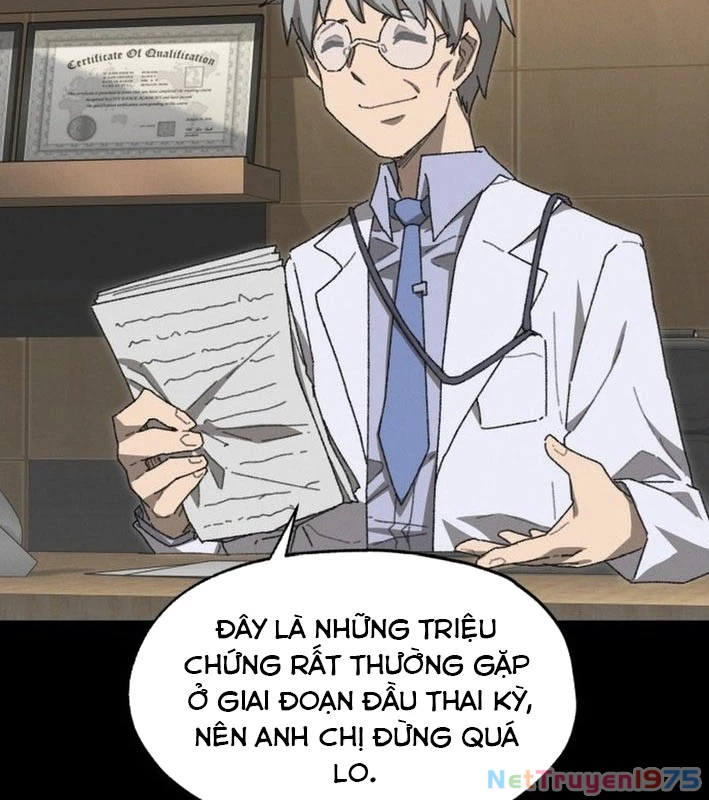

Kẻ Chôn Cất Quái Vật - Chapter 1